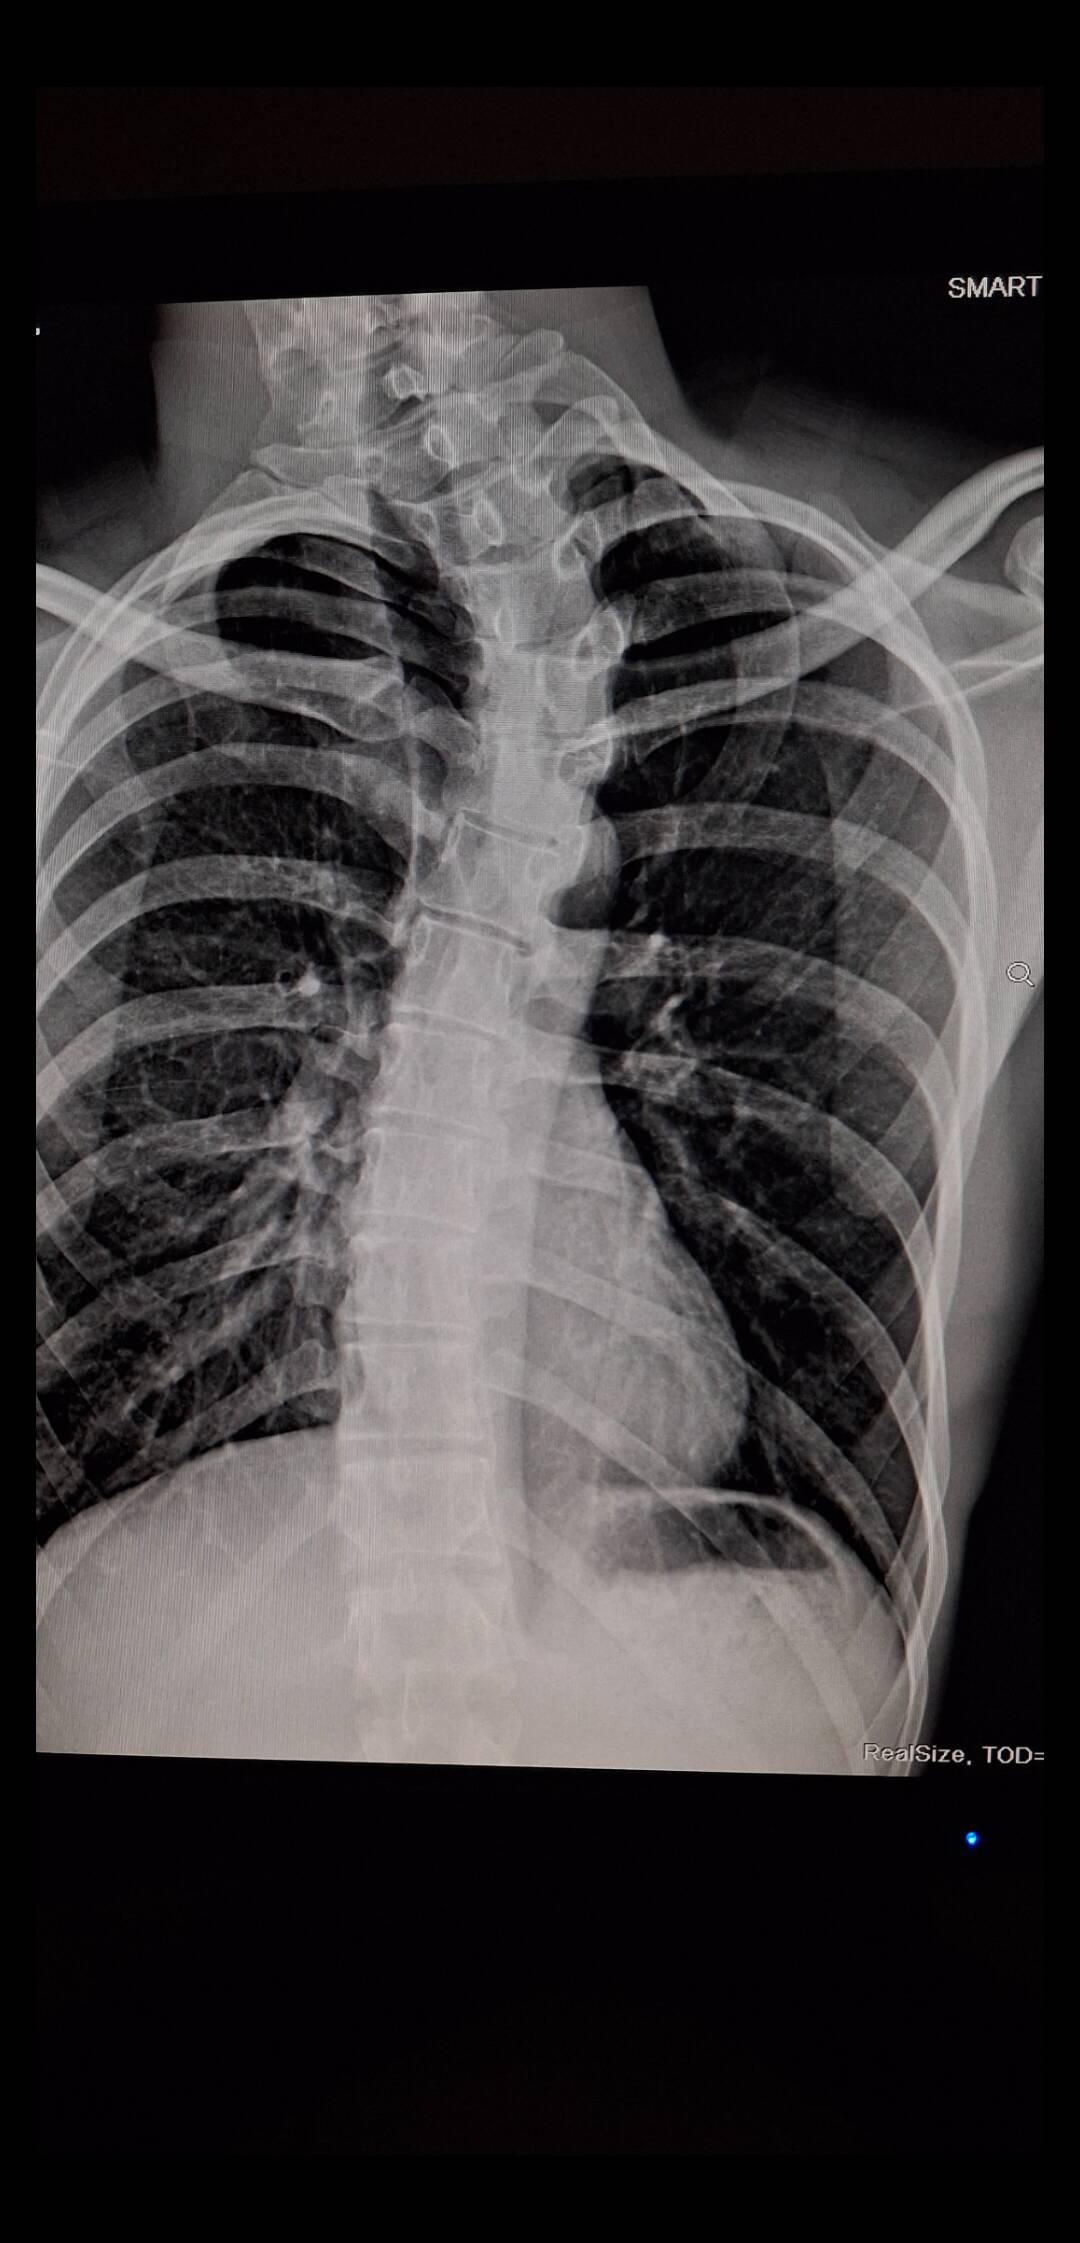

“Just a lung checkup & found out I was born bent.”

So my lungs are basically fine, but my spine is out here living its own life story. Getting an unexpected plot twist from a routine checkup—at least now I know why I never quite stand up straight in family photos.